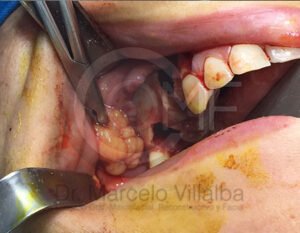

Antes de la extracción se realiza una valoración clínica y estudios de imagen, como radiografías panorámicas o tomografías, para conocer la posición del tercer molar, su relación con los nervios y planificar un procedimiento seguro y adecuado para cada paciente.

No es recomendable. Antes de extraer terceros molares es necesario realizar una valoración clínica y estudios de imagen para conocer la posición del diente, su relación con los nervios y el tipo de procedimiento más seguro para cada paciente.

Algunas extracciones simples de otras piezas dentales pueden ser realizadas por un odontólogo general; sin embargo, por la complejidad que presentan los terceros molares, o si se encuentran retenidos, impactados o cerca de estructuras importantes, se recomienda que el procedimiento sea realizado por un cirujano maxilofacial para mayor seguridad y control del tratamiento.